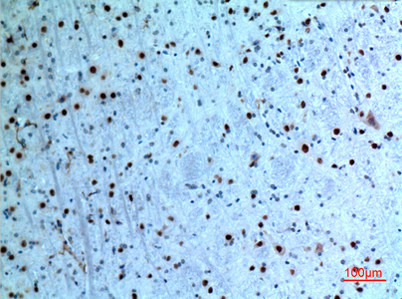

| Dilutions: | Western Blot: 1/500 - 1/2000. IHC-p: 1:100-300 ELISA: 1/20000. Not yet tested in other applications. |